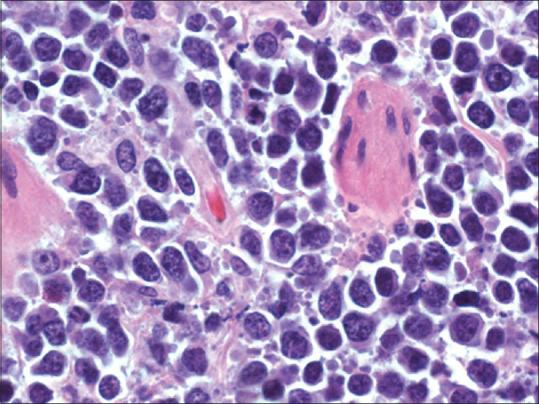

Gallbladder involvement in lymphoma is rare, with only a few cases reported in the literature, predominately in the pre positron emission tomography (PET) era. F-fluorodeoxyglucose (F-FDG) PET/computed tomography (CT) has now become the modality of choice in the staging of lymphoma. We report a case of gallbladder involvement by high-grade B-cell lymphoma detected by PET/CT.